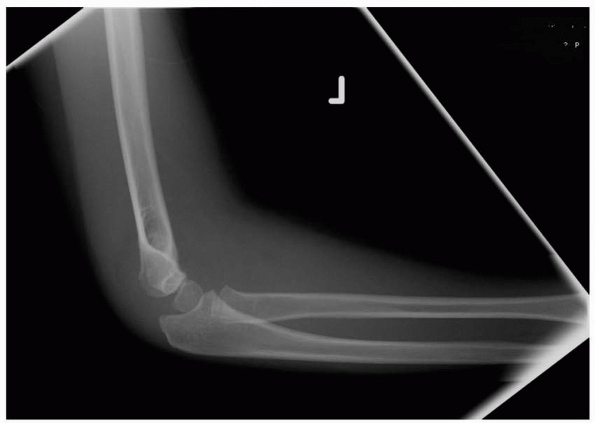

loss of normal alignment in fractures with comminution and collapse of

the medial column (Fig. 14-7). Medial collapse

signifies malrotation in the frontal plane (which defines the injury as

at least a type III fracture) and is associated with a loss of the

Baumann angle and varus malalignment. The lateral view (Fig. 14-8)

may show reasonable alignment, which may lead to an underappreciation

of the seriousness of this fracture, which requires operative

reduction. Bahk et al.16 reported